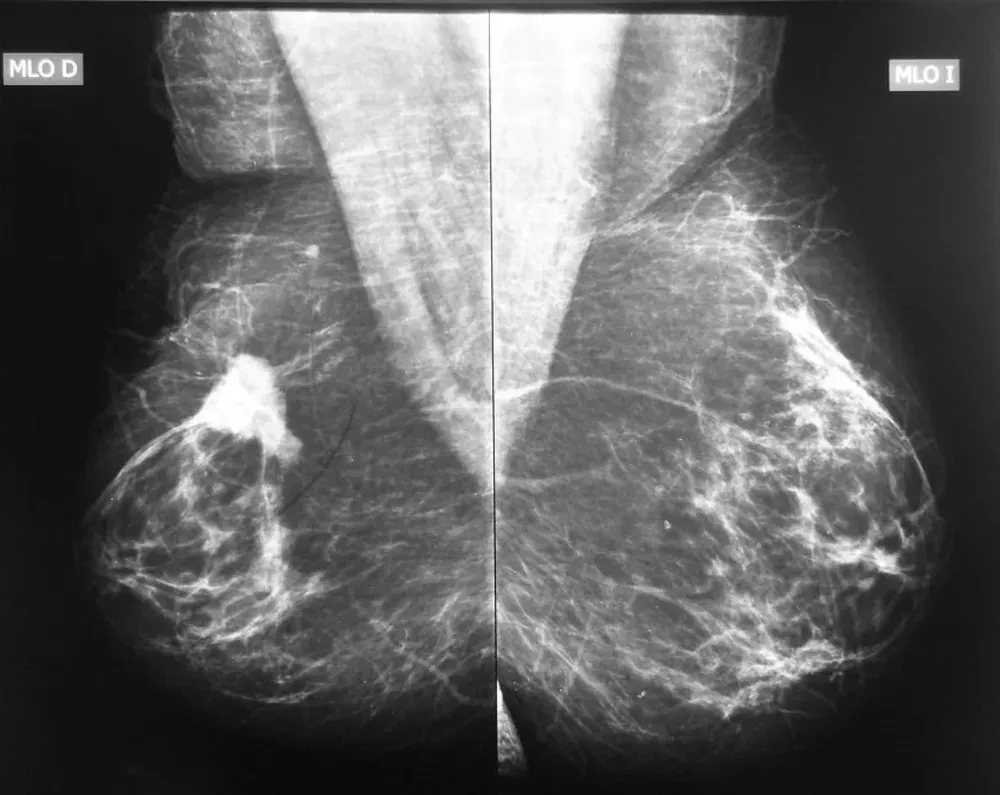

"La preocupación por la radiación me parece que debería ser absolutamente menor, comparado con otros problemas como que en la imagen de la mamografía la información que se genera a veces no es del todo clara y eso genera procedimientos adicionales que a veces hubiesen sido innecesarios", manifestó González.

"Es verdad que no hay físicos médicos trabajando para las mamografías y es deseable que lo haya", reconoció el experto, quien considera que se puede tener la dosis adecuada de radiación pero si la calidad de la imagen que genera de la mama es mala, puede inducir sobrediagnósticos.

En ese sentido, el profesor titular de la clínica ginecotológica de la Facultad de Medicina y exsubsecretario del Ministerio de Salud Pública, Leonel Briozzo, reconoció que gran cantidad de los mamógrafos de Uruguay son añosos. "Hubo después del 2005 una fuerte modificación de los equipos, pero siguen habiendo muchos que son muy antiguos y eso influye mucho en la radiación de la mama y en los falsos positivos", dijo.

La alta cantidad de diagnósticos erróneos fue una de las razones por las que el MSP determinó cambios en la periodicidad en la que deben realizarse las mamografías. Los falsos positivos pueden alcanzar 30% y es por eso la Administración de Servicios de Salud del Estado instaló un sistema automático de detección de tumores.

Sin embargo, el Instituto Nacional del Cáncer –centro de referencia en oncología del país para los usuarios de ASSE– acaba de instalar una máquina que funciona como un sistema automático de diagnóstico. Eso ayuda a disminuir errores en la detección de tumores que pueden ser cancerígenos, que muchas veces son inducidos por mala interpretación de los médicos o falta de calidad en las imágenes.

Según la Agencia para la Investigación en Salud y Directrices de Calidad de Estados Unidos, entre 20 y el 30% de las mujeres que se realizan mamografías tienen un falso positivo que requiere estudios complementarios. Esos datos, de 2011, fueron citados en la Guía de detección temprana de Cáncer de mama de 2015 del Ministerio de Salud Pública. En muchos casos esto puede producir biopsias innecesarias. La instalación busca reducir esa cantidad de malos diagnósticos.